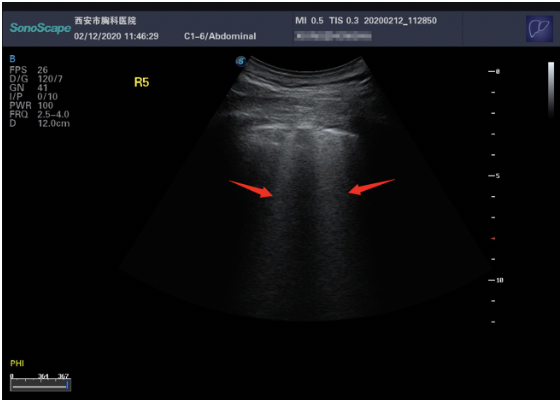

What do you see on ultrasound?

There are five views provided, covering various portions of the left and right lungs. There are diffuse, multifocal B-lines bilaterally, most confluent in the left anterior superior view. The left lateral mid view demonstrates sub pleural consolidation as well as irregular thickening of the pleural line.

Studies by Peng et al. and Huang et al., each examining a distinct population of 20 patients in different parts of China, provide the first data on lung ultrasound findings in CoVID-19 pneumonia patients as they correlate with CT findings. They note that their ultrasound findings correlated well with CT findings, are often present prior to any lesions on chest radiography, and are consistent with findings in other viral pneumonia syndromes. The findings, seen in the figures below, include:

Sub-pleural consolidations, often multifocal, appearing as hypoechoic “bites” out of the lung parenchyma. This can sometimes be seen in conjunction with hyperechoic air bronchograms, with B-lines emanating distally from the consolidations.

Consistently with the study by Zhao et al. the authors remark that the lesions are often multifocal, multilobar, and are infrequently associated with pleural effusions. The following representative images are derived from the study by Huang et al.

Figure3. Irregular-appearing pleura with subpleural consolidations and air bronchograms, from Huang et al.